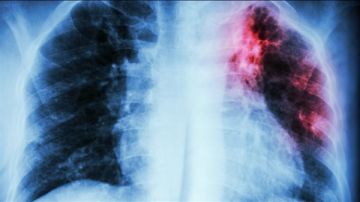

قد يكون العلماء على وشك تطوير لقاح جديد لمكافحة مرض السل، أحد أخطر الأمراض في العالم.

لكن، بحسب 'دايلي ميل'، لا يزال السل يحصد أرواح أكثر من مليون شخص سنوياً، وهو مرض فتاك بشكل خاص في البلدان النامية حيث يكون الوصول إلى المضادات الحيوية الحديثة محدوداً.

وقد جعلت مقاومة المرض لبعض الأدوية السبب الرئيسي للوفيات المعدية عالمياً.

كما أن اللقاح الحالي أقل حماية للبالغين على الرغم من فاعليته للأطفال، وخاصة في المناطق ذات معدل انتشار مرتفع للسل.